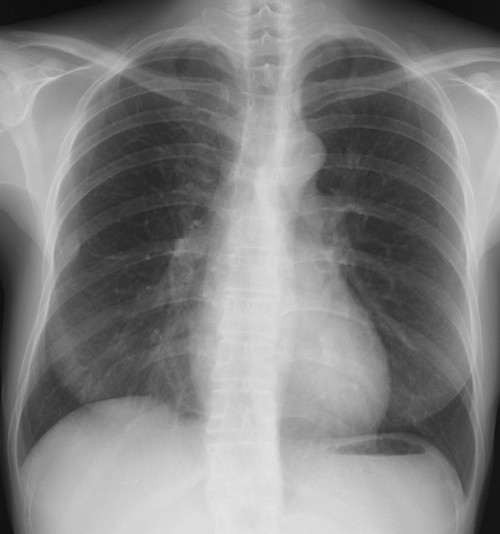

何処に異常陰影があるでしょうか?

肩甲骨に重なって見逃しやすいが、仮骨形成が始まった右第7肋骨骨折を診断できる。

右第4肋骨と胸椎の肋骨頭関節に関節面に一致して陰影をみとめる。

左鎖骨、胸鎖関節に近接した約1.5cmの円形陰影があり、辺縁は不規則(毛羽立ってみえる)になっている。陰影は大動脈・縦隔とのシルエットサインはみられず左肺S1+2に存在すると考えられ、肺門部のリンパ節腫脹はみられない。

縦隔陰影の拡大、大動脈の拡張をみとめる。右肺門肺動脈に重なって半球様の陰影(径2.7cm)が確認できる。肺門のリンパ節腫大等はない。

[評価]S6の炎症性偽腫瘍、結核、肺がん等の可能性がありCT等の検索・喀痰細胞診・生検が必要になる。